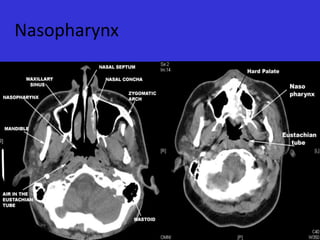

Nasopharynx